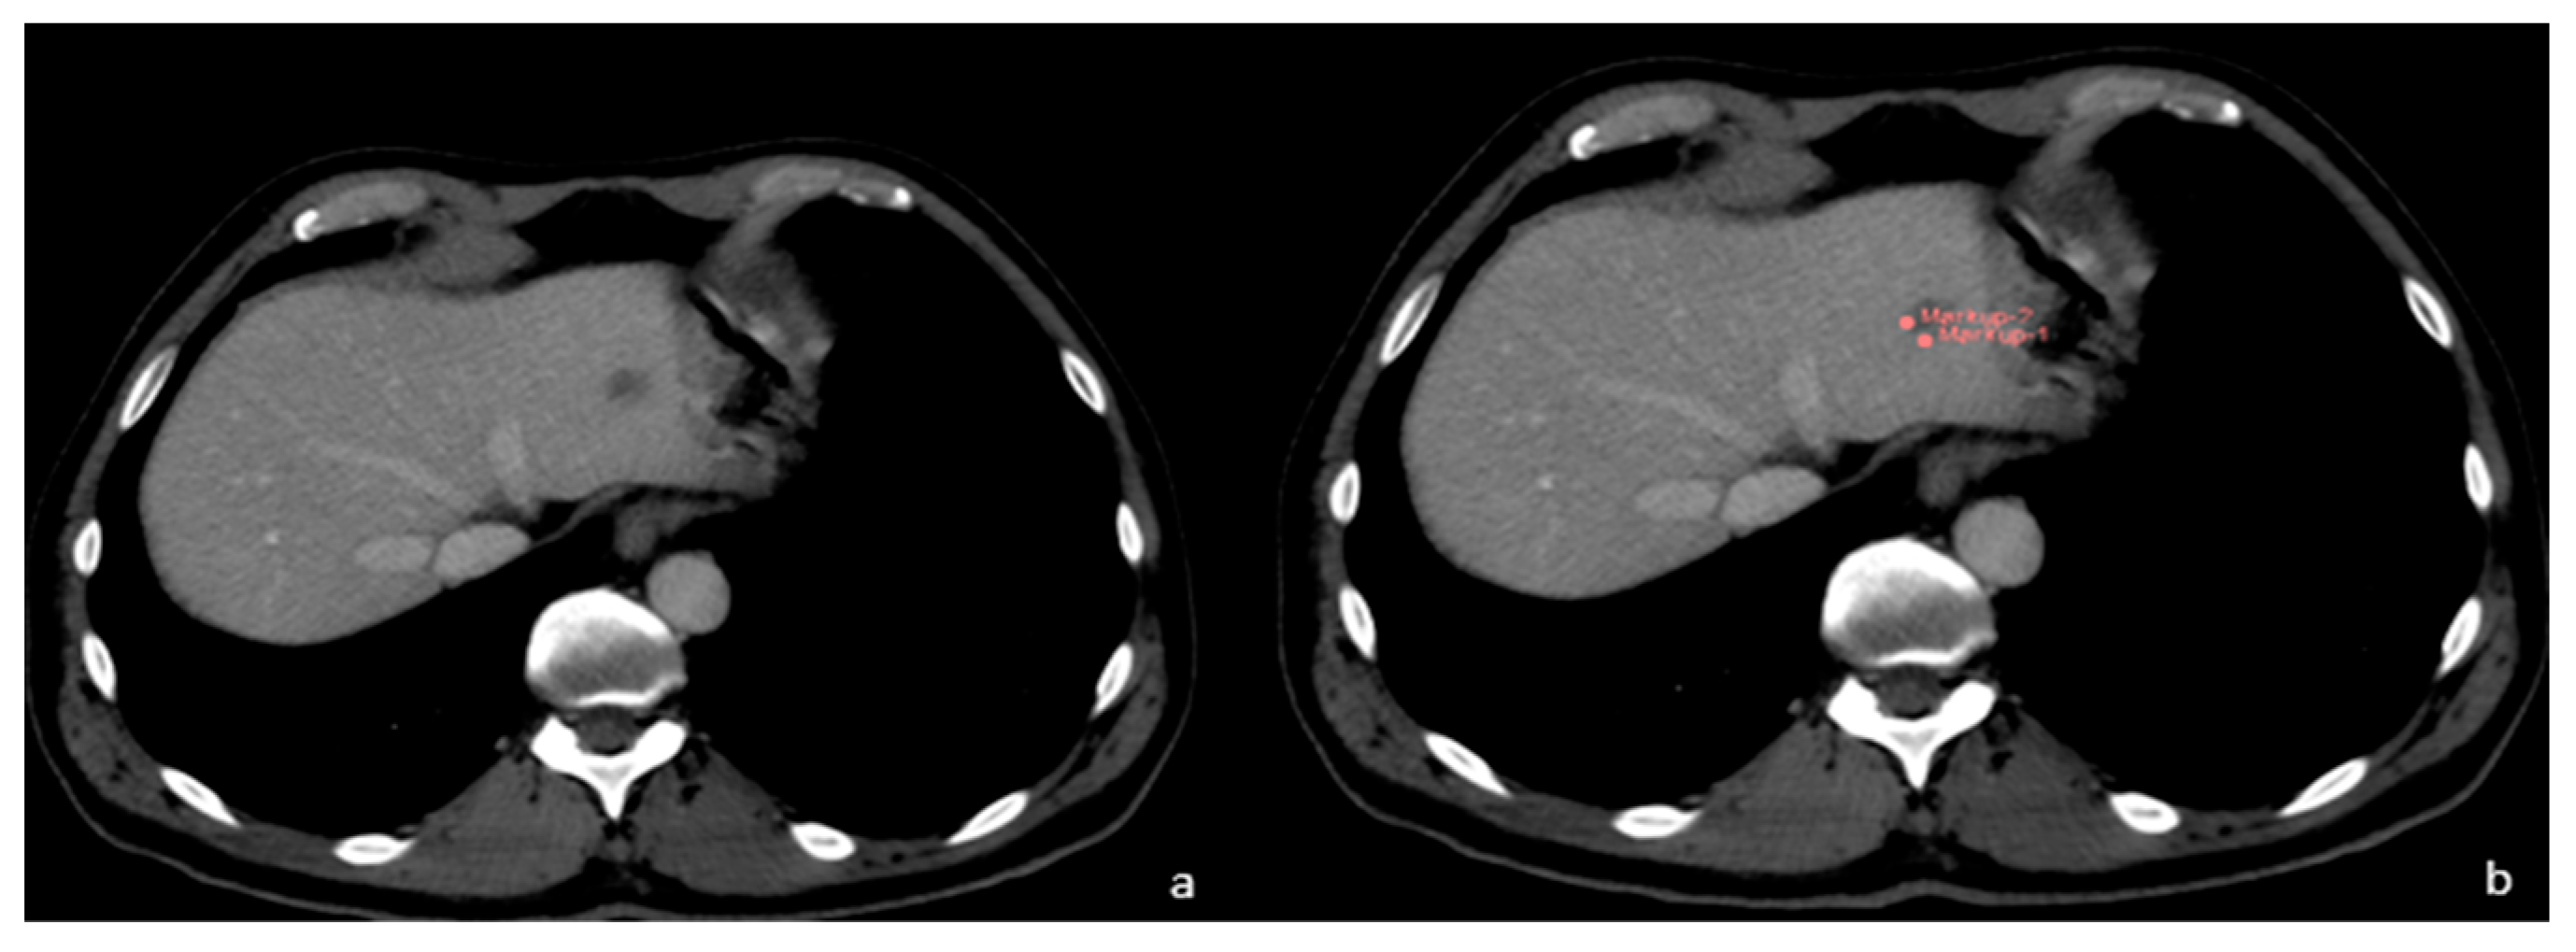

3. Malignant CT Features

4. Benign Radiomics CT Features